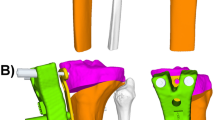

3D hybrid

3D planning for lower extremity realignment surgery represents the state-of-the art method at our institution. After preliminary planning of realignment surgery in 3D NWB CT [2], the definitive planned opening angle is manually adapted by the treating surgeon after considering the extent of deformity in standing LLR and is therefore referred to as 3D hybrid. Increasing the initially suggested opening angle of the 3D NWB plan was considered in patients with increased HKA in LLR compared to the 3D NWB model, to adjust for the missing WB state in the 3D models. For each 3D model, HKA pre and HKA post were measured as the projected 2D angle in the frontal plane between a line defined by hip and knee center, and a line defined by knee and ankle center. The medial opening angle of the tibia was calculated around a single 3D axis of rotation. This 3D planning modality has been previously described and demonstrated excellent reliability [2, 5, 17] (Fig. 1, left).

Overview of planning modalities. The planned correction of the mechanical leg axis was analyzed in 3D hybrid (left), 3D non-weight-bearing (NWB) (middle) and 3D weight-bearing (WB) modality (right) for each patient. Left: 3D hybrid is based on NWB 3D CT models and adapted by the surgeon after consideration of WB information from the long-leg-radiograph (LLR) (red box). Middle: 3D NWB relies solely on NWB information from supine acquired 3D CT models. Right: 3D WB allowed the analysis of 3D models in the WB-state after 3D/2D registration of NWB CT models onto standing LLR. The mannikin indicates the lying or standing position during image acquisition for each modality

3D non-weight-bearing (NWB)

3D NWB planning relies solely on the CT models obtained in a supine position without additional information of the WB state. The protocol included exactly the same CT scan, creation of 3D models, definition of joint centers and measurements as described above for the 3D hybrid method. However, the deformity analysis and correction were based on supine imaging only and the WB state was not considered (Fig. 1, middle).

3D (weight-bearing (WB)

The consideration of the WB state in 3D planning represents a novel planning modality [11]. An intensity-based algorithm was used to register NWB CT scans onto standing LLR to transform the patient-specific 3D models into the WB state. After annotation of the corresponding anatomical landmarks (ankle center, knee center, hip center) in EOS and CT NWB [11], the registration algorithm detects the optimal position by comparing intensity values between the LLR and digitally reconstructed radiographs (DRR) generated from CT using the same geometry as the EOS system [18]. The registration was executed using ImFusion Suite software (ImFusion GmbH, Munich, Germany). Once registration to the WB state was completed, the measurement of HKA pre and HKA post was performed as described for the 3D hybrid method (Fig. 1, right).